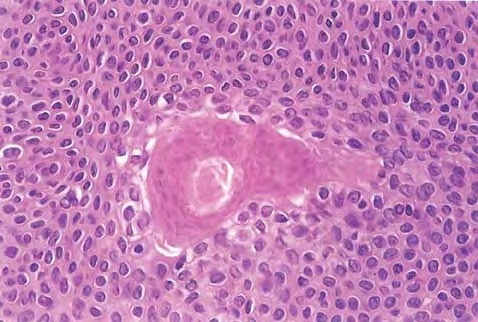

Hidroacanthoma simplex shows sharply demarcated aggregations of cuboid to ovoid cells confined to the epidermis. Eccrine poroma reveals aggregations of uniform basaloid cells that radiate from the basal layer of the epidermis into the dermis . Dermal duct tumor consists of several sharply circumscribed, mainly dermal nodules composed of poroid and cuticular cells. Ductal structures are frequently observed. Poroid hidradenoma is characterized by intradermal, solid, and cystic aggregations of poroid cells.